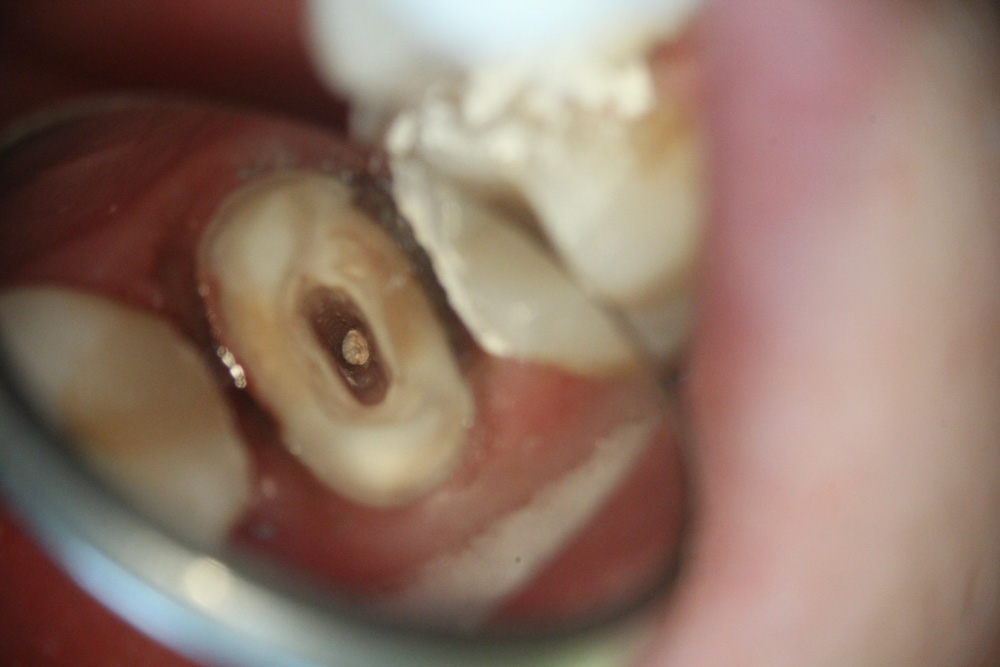

C’est initialement en endodontie (soins des racines dentaires, lorsque la dent ne peut plus être conservée vivante) que le microscope a trouvé son argument majeur. Les soins endodontiques sont spécifiques dans la mesure où ils sont effectués à l’intérieur de la cavité pulpaire de la dent : le praticien travaille en aveugle, en se basant uniquement sur sa perception tactile. Grâce au microscope «l’oeil est transporté au bout du doigt» permettant à l’opérateur d’observer et de diriger finement le travail de ses instruments à l’intérieur des racines. Les séances de traitements de racines, réputées longues, difficiles, éprouvantes pour le dentiste et le patient et caractérisés par des résultats aléatoires, deviennent ainsi beaucoup plus fiables. Le microscope trouve ici un domaine d’intervention majeur en apportant confort de travail pour le praticien et bénéfice pour le patient, grâce à un réel gain en terme de fiabilité et de prédictibilité du résultat endodontique. De surcroît, le microscope permet des prouesses techniques telles que l’élimination d’instruments cassés à l’intérieur des racines, le comblement de perforations dentaires, l’obturation canalaire des racines immatures et résorbées....

En odontologie conservatrice, la pratique des soins restaurateurs s’en trouve significativement bouleversée. Les cavités de caries peuvent être traitées par de nouvelles méthodes moins mutilantes. Grâce au contrôle visuel permanent, le chirurgien dentiste bénéficie d’une action très sélective : il parvient à n’éliminer que les seuls tissus dentaires cariés, en réalisant des minicavités et des miniobturations dentaires préservant ainsi la résistance mécanique des dents, moins susceptibles de se fracturer ultérieurement. La mise en place des matériaux de restauration dentaire, en particulier des matériaux adhésifs, est également facilitée : la qualité des joints augmente, permettant des obturations plus étanches moins sujettes aux sensibilités post-opératoires et aux récidives de caries. La finition et le polissage des résines composites sous microscope permettent de rendre les obturations quasiment invisibles. Ainsi, microdentisterie est aussi synonyme d’esthétique.